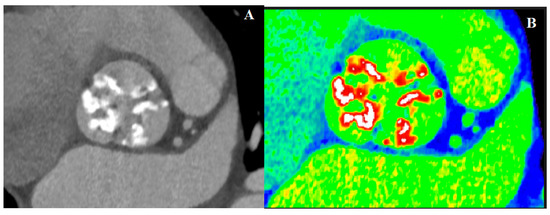

4.2. Computed Tomography in AS